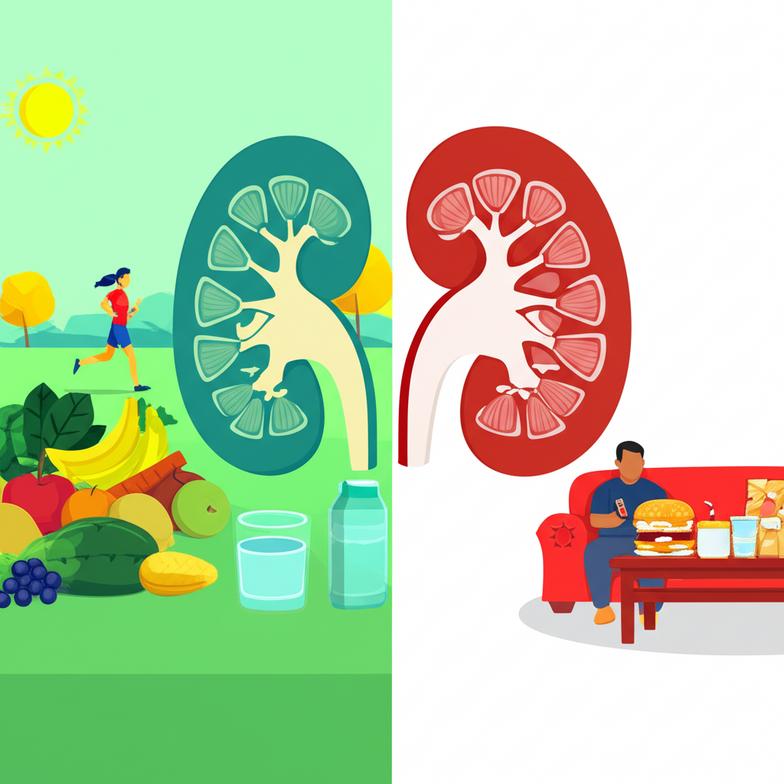

ปัจจัยเสี่ยงด้านโภชนาการและไลฟ์สไตล์ที่ส่งผลต่อสุขภาพไต

ในมุมมองของเวชศาสตร์ชะลอวัย เราเชื่อว่าปัญหาสุขภาพส่วนใหญ่ รวมถึงภาวะไตเสื่อม มีรากฐานมาจากการดำเนินชีวิตและพฤติกรรมการกินที่ไม่สมดุล ปัจจัยเหล่านี้มักสะสมมาเป็นระยะเวลานาน และสามารถแก้ไขได้ด้วยการปรับเปลี่ยนพฤติกรรมอย่างมีวินัย

- การขาดการออกกำลังกาย: การเคลื่อนไหวที่น้อยเกินไปส่งผลต่อการเผาผลาญ และเพิ่มความเสี่ยงต่อโรคอ้วนและเบาหวาน ซึ่งเป็นสาเหตุทางอ้อมที่ทำให้ไตเสื่อม

การตระหนักถึงปัจจัยเหล่านี้คือจุดเริ่มต้นของการสร้างสุขภาพไตที่ดีและยั่งยืน การปรับเปลี่ยนไลฟ์สไตล์และโภชนาการจึงเป็นก้าวแรกที่สำคัญและจำเป็น.

- การออกกำลังกายที่เหมาะสม: การออกกำลังกายอย่างสม่ำเสมอในระดับปานกลาง ช่วยส่งเสริมการไหลเวียนเลือด ควบคุมความดันโลหิตและระดับน้ำตาลในเลือด ลดความเสี่ยงต่อโรคอ้วน ซึ่งส่งผลต่อสุขภาพไต